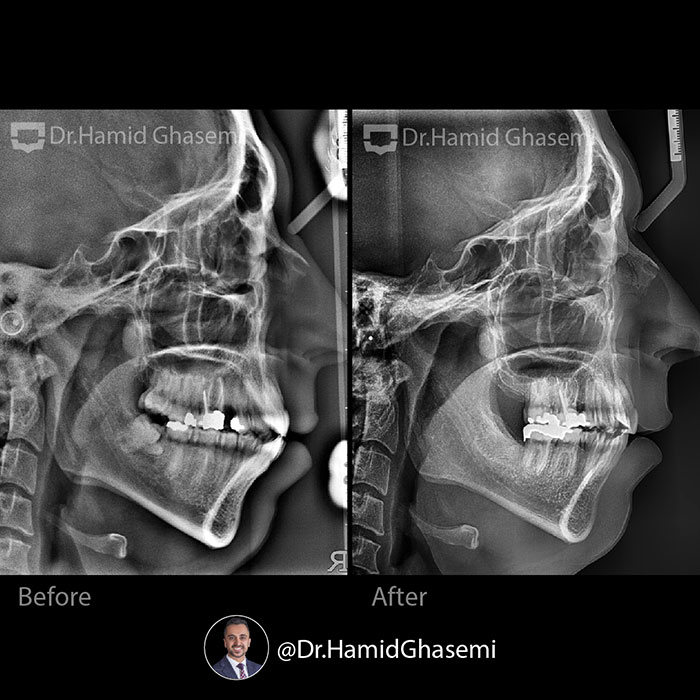

درمان ارتودنسی بدون جراحی فک در کیس همراه با جلوزدگی هر دو فک در مدت ۲۲ ماه انجام شد.

Non surgical orthodontic treatment of case with bimaxillary dentoalveolar protrusion done within 22 months.